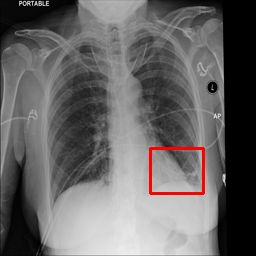

Deployments of artificial intelligence in medical diagnostics mandate not just accuracy and efficacy but also trust, emphasizing the need for explainability in machine decisions. The recent trend in automated medical image diagnostics leans towards the deployment of Transformer-based architectures, credited to their impressive capabilities. Since the self-attention feature of transformers contributes towards identifying crucial regions during the classification process, they enhance the trustability of the methods. However, the complex intricacies of these attention mechanisms may fall short of effectively pinpointing the regions of interest directly influencing AI decisions. Our research endeavors to innovate a unique attention block that underscores the correlation between 'regions' rather than 'pixels'. To address this challenge, we introduce an innovative system grounded in prototype learning, featuring an advanced self-attention mechanism that goes beyond conventional ad-hoc visual explanation techniques by offering comprehensible visual insights. A combined quantitative and qualitative methodological approach was used to demonstrate the effectiveness of the proposed method on the large-scale NIH chest X-ray dataset. Experimental results showed that our proposed method offers a promising direction for explainability, which can lead to the development of more trustable systems, which can facilitate easier and rapid adoption of such technology into routine clinics. The code is available at www.github.com/NUBagcilab/r2r_proto.